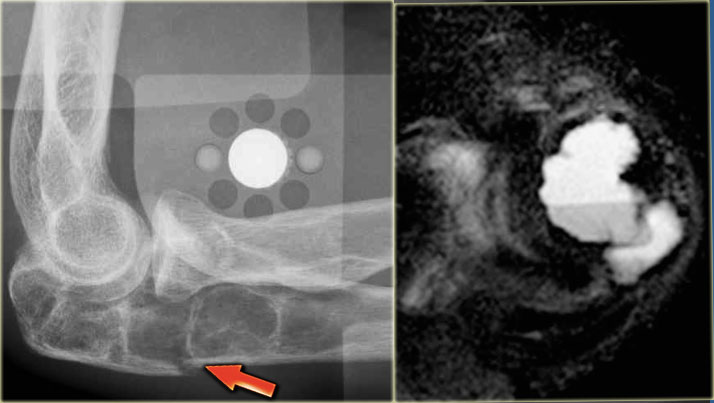

Brown tumor (2)

On the left images of a 30-year-old male with well-defined lytic lesion of the olecranon.

On the radiograph several ridges can be seen and a pathologic fracture (arrow).

The T2-weighted image with fat saturation demonstrates fluid-levels due to sedimentation.

Most likely diagnosis: giant cell tumor and ABC.

Biopsy revealed brown tumor.